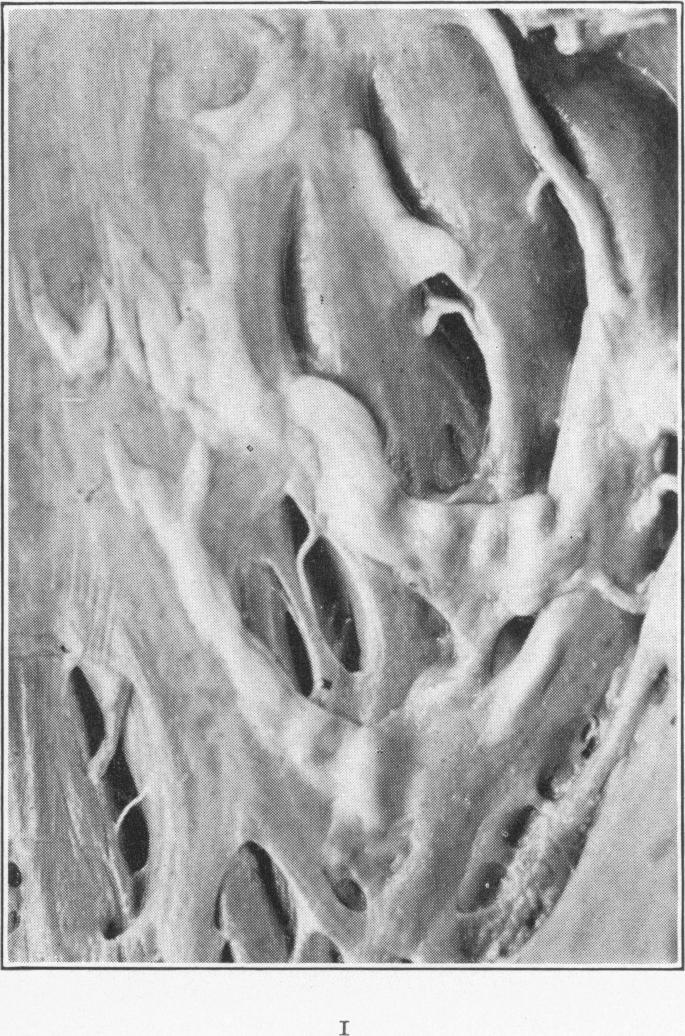

Endocardial Pockets.

Am J Pathol. 1930 Nov;6(6):733-748.5.